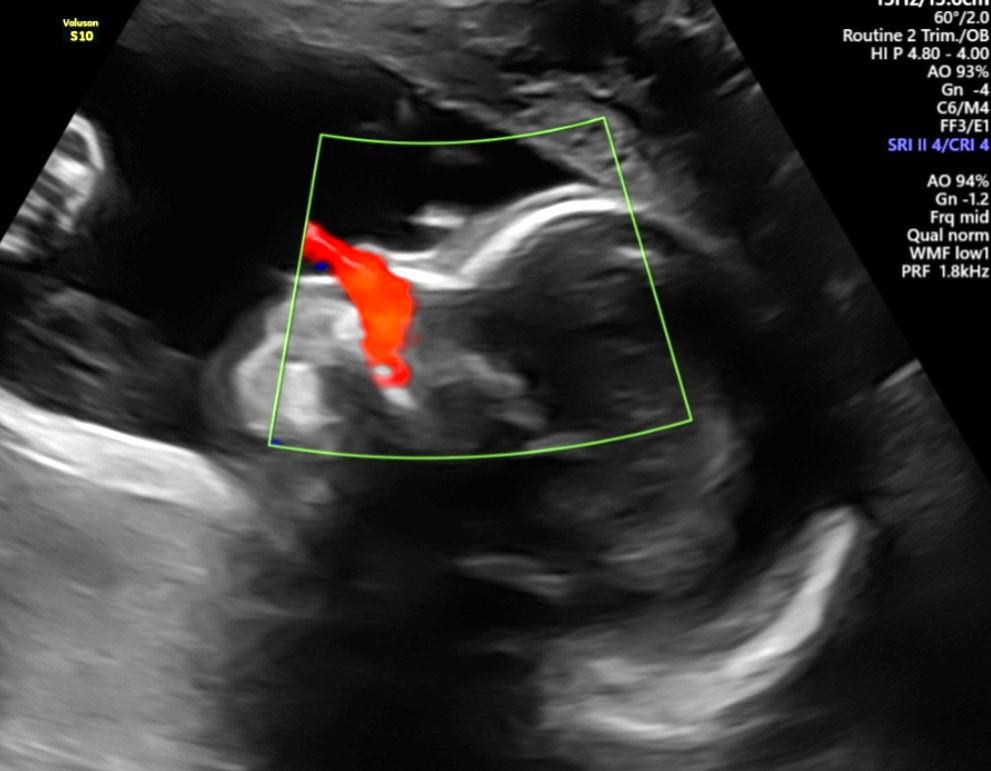

- Ultrassom Obstétrico

- Ultrassom Obstétrico Transvaginal de Primeiro Trimestre

- Ultrassom Obstétrico com Avaliação da Translucência Nucal

- Ultrassom Morfológico de 1º Trimestre

- Ultrassom Morfológico do 2º Trimestre

- Ultrassom Obstétrico com Doppler

- Ultrassom Endovaginal para Rastreio de Prematuridade

- Ultrassonografia em 3D/4D

- Perfil Biofísico Fetal

- Cardiotocografia Fetal Anteparto

- Ecocardiografia Fetal